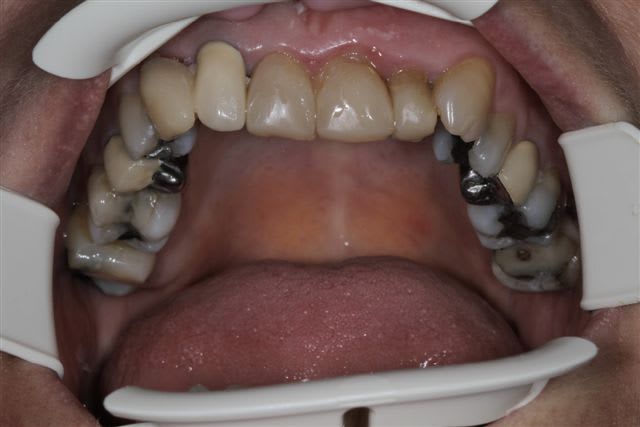

N'hésitiez pas çà me donner votre avis, patiente 47 ans ne supporte plus ses antérieurs, maquillées à la résine il y a quelques années.

Pas de demande concernant l'occlusion, ni les postérieurs, à fait des économies et veux s'offrir "un sourire", sur fond propre budget envisageable au départ 4000€

C'est un cas de réhab global, ortho et 28 couronnes.

Les secteurs post sont en mauvais état, l'occlusion est moche, et si tu ne fais que le sourire, tu auras de drôle de résultat et des casses de céram ou bien des antagonistes.

Vu les axes actuels des antérieures, soit tu gardes la même forme et les mêmes axes et tu auras de dents assorties mais pas vriament plus esthétiques. Sinon c'est ortho et la totale. Si tu changes la forme sans amélioration de l'esthétique ce sera l'echec mécanique assuré.

Je suis assez d'accord avec Ceramik, ce qui me saute aux yeux,outre l'esthétique bien sur, ce sont les courbes occlusales de la patiente, notamment secteur 2 et 3 en postérieurs(26 ne semble pas en occlusion, et 27 sur une pointe).

Le secteur antérieur doit donc supporter pas mal de contraintes... d'autant plus que le guide incisif semble assez fermé.

Perso, je ne toucherai à rien en antérieur,( d'autant plus avec du tout céram) tant que les courbes postérieures ne sont pas rétablies.